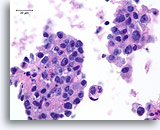

Atypische proliferatieve ductale laesie, Borst FNA, Diff-Quick gekleurde uitstrijk.

De ductale cellen zijn in drie dimensies opgestapeld. Er is geen duidelijke populatie myoepitheliale cellen en linksonder is er slechts focaal mogelijk gedeelde polariteit van aangrenzende ductale cellen.

Atypische proliferatieve ductale laesie, Borst FNA, Diff-Quick gekleurde uitstrijk.

De ductale cellen zijn in drie dimensies opgestapeld. Er is geen duidelijke populatie myoepitheliale cellen en linksonder is er slechts focaal mogelijk gedeelde polariteit van aangrenzende ductale cellen.